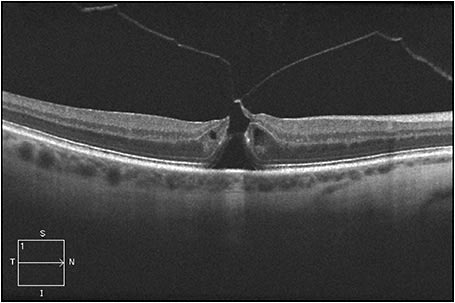

Figure 1 shows an eye in this series, with FTMH measuring 216 µm and concurrent focal VMT; this patient’s best-corrected Snellen VA was 20/70. Figure 2 shows VMT release following intravitreal ocriplasmin, with a decrease in VA to 20/200 at one week following injection. Figure 3 demonstrates an increase in FTMH size (now measuring 264 µm) at 12 days following injection.

Figure 2. VMT release following intravitreal ocriplasmin, with a decrease in VA to 20/200 at one week following injection.